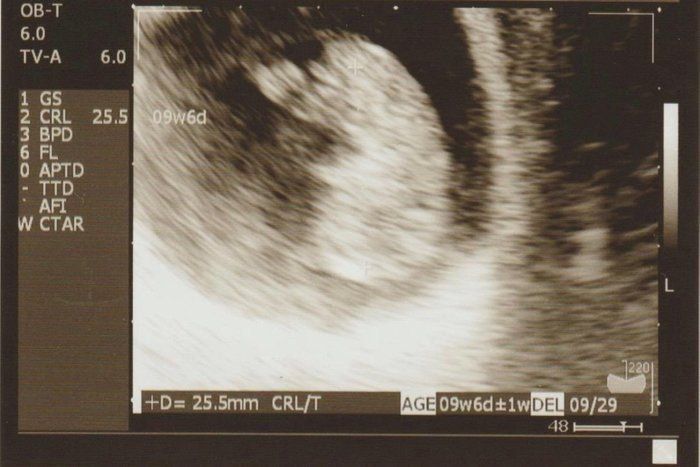

チャーミー小結さんの妊娠9週目のエコー写真

何となく頭と胴体の区別が出始めました。スリムな人だとまだおなかの膨らみが分からない頃ですが、嬉しくてウエストノーマークのマタニティ服を着て過ごしていました。